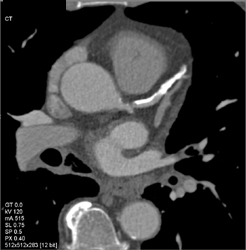

Diseased LAD and Circumflex Artery (CX) With Extensive Calcification